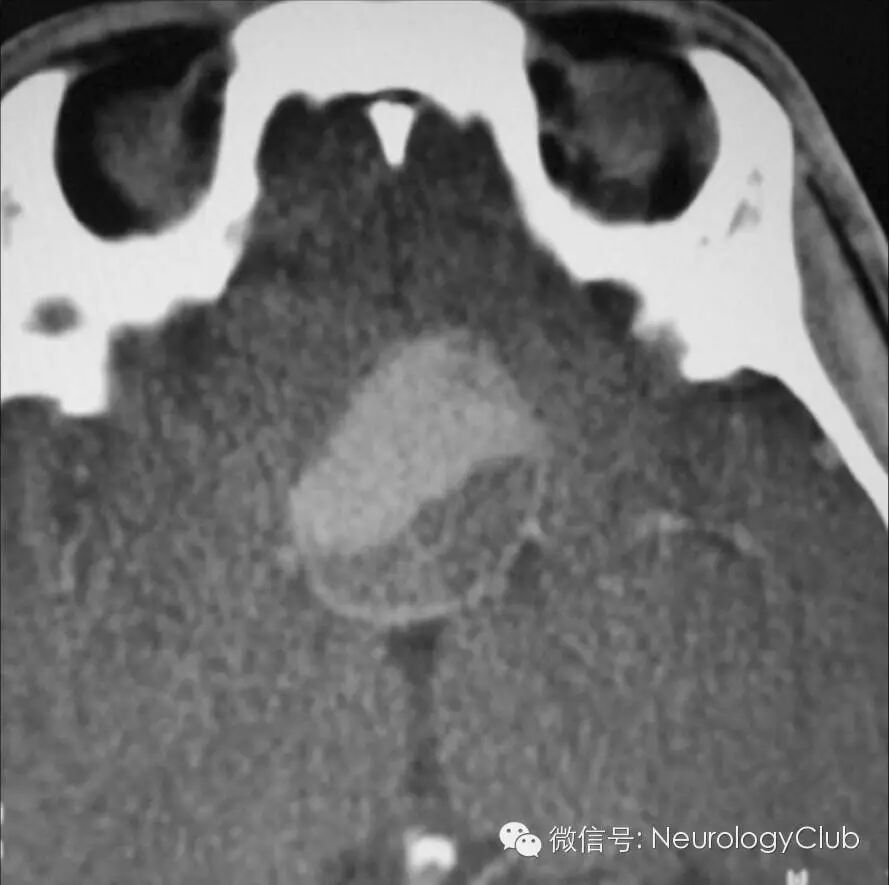

阴阳征表现为增强CT上,在扩张的卵圆形动脉截面内,可见半强化和半无强化区,形态酷似道教的阴阳符号。

阴阳征见于附壁血栓形成的真性和假性动脉瘤患者。动脉瘤为局限性或弥漫性的动脉管腔扩张,大于其正常直径的50%。假性动脉瘤指动脉管壁被撕裂或穿破,血液自此破口流出而被主动脉邻近的组织包裹而形成血肿,多由创伤所致。大动脉瘤和假性动脉瘤容易形成附壁血栓,因此血流仅充盈部分管腔。阴阳征中,造影剂充盈增强的部分代表通畅的管腔,而无造影剂充盈的部分则代表附壁血栓的形成。

病例1:颅内动脉瘤患者